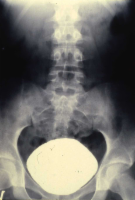

Die Behandlung umfasste neben der perkutanen, transluminalen Dilatation der A. renalis die systemische Behandlung mit Cortison und β-Blocker. Unter dieser Behandlung kam es zur Verbesserung der linksseitigen Nierenfunktion auf 30%. Das AUR zeigte eine zeitgerechte Kontrastmittelausscheidung (Abbildung 20). Im weiteren Verlauf ist evtl. eine neuerliche Dilatation erforderlich bzw. eine operative Versorgung der Nierenarterienstenose.